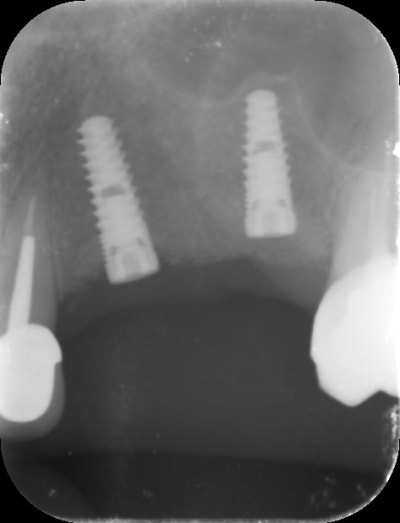

regarde moi ça pxav c'est la suite de mon cas

-> crete de 2 mm , expansion pour mettre du 3.7 sur 13 et 15 + summers dans la même séance sur 15

-> et regarde voir 6 mois après on voit que la 15 s'est légèrement enfoncée sur 2 mm :))))) expansion + summers ça faisait peut être beaucoup.

-> je lui ai posé les vis

-> Et je vais devoir exceptionnellement faire dès pilier CFAO pour corriger très légèrement l'axe (Implants légèrement vestibulés)

Photo 1 expansion plus summers

Photo 2-3 : 6 mois après

est ce que sur la pano que je poste ces Implants postérieurs sont dans l'axe ? 😊 Est ce que ça pose problème ? J'ai pas l'impression 😊😊😊. Alors tu vas peut être me dire que c'est différent : on est dans des divergences d'axe dans le sens mesio-distal et non vestibulo lingual. Mais Ils ne sont pas tout à fait dans l'axe des dents on dirait, non ? Alors si on extrapole est ce que la ptite divergence d'axe dans un cas comme Le mien pose problème alors qu'au départ il n'y avait quasi pas d'os , ni en largeur ni En hauteur...